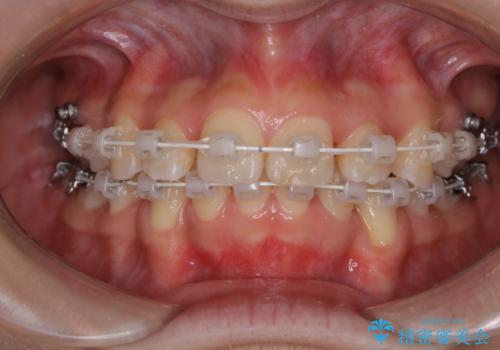

- 矯正装置

- 審美装置(ワイヤー)

- 出っ歯が気になるとご相談にいらした方です。抜歯して歯を並べました。深かった噛み合わせも改善させることが出来ました。